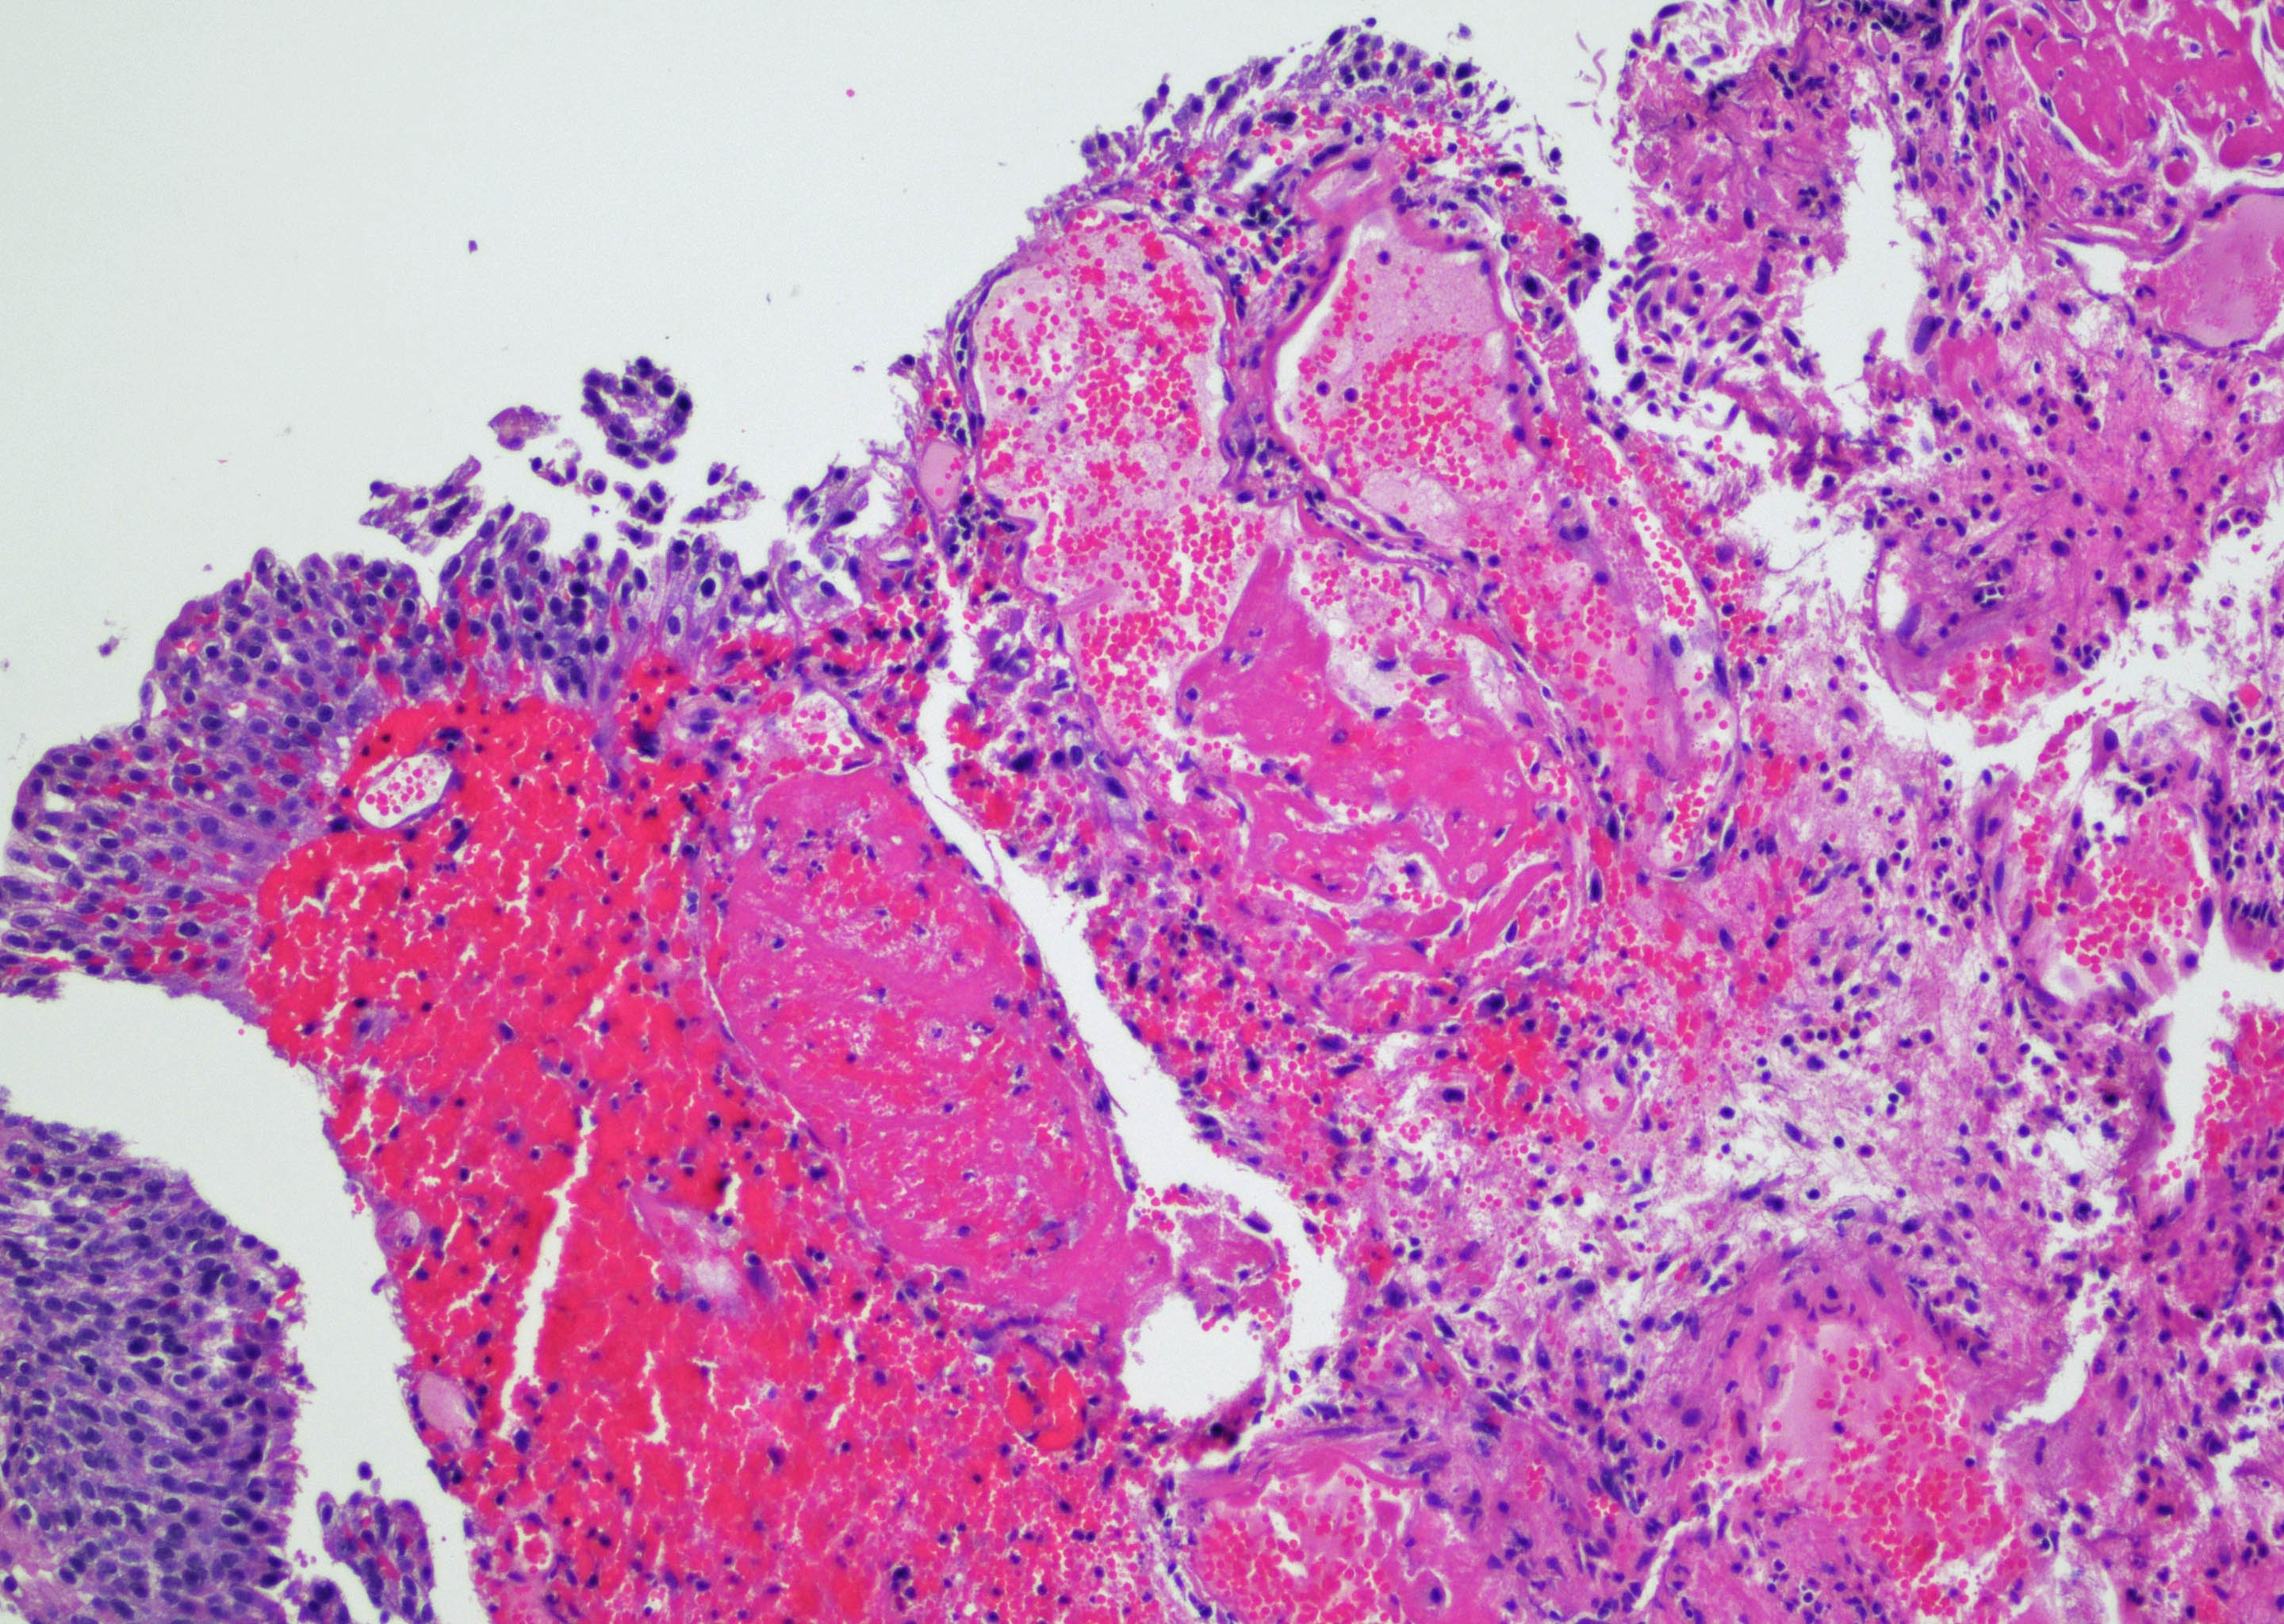

- Vessels with fibrin thrombi, fibrinoid vascular necrosis, vascular congestion, thickened walls, endothelial proliferation and telangiectasia

- Acute and chronic inflammation

- Reactive multinucleated stromal fibroblasts with smudgy nuclei

- Fibrosis and edema

- Hemorrhage and hemosiderin

- Urothelium can show

- Nuclei with variation in nuclear size and shape, hyperchromasia, vesicular or smudgy chromatin

- Eosinophilic or amphophilic cytoplasm, cytoplasmic vacuoles

- Multinucleated giant cells (Am J Surg Pathol 2008;32:92)

- Usually no mitotic figures

- Surface erosion, ulceration

- Squamous metaplasia

- Pseudocarcinomatous urothelial hyperplasia: variable sized urothelial cords and nests with rounded or irregular edges present in the lamina propria and enclose dilated blood vessels with fibrin deposition (Am J Surg Pathol 2008;32:92)

- Acute phase: edematous, congested and telangiectatic vessels, acute and chronic inflammatory infiltrate, atypical stromal cells with multinucleated forms

- Chronic phase: atrophic urothelium, atrophic smooth muscle layer, collagen deposition (fibrosis) (Am J Surg Pathol 2004;28:909)

Microscopic (histologic) images

Contributed by Y. Albert Yeh, M.D., Ph.D. and Jennifer Lee, M.D.

- Comment: There is a history of radiation therapy per the medical record. The transurethral resection of the bladder lesion shows fragments of urothelial mucosa with total and partial denudation of urothelium. The urothelial lining cells show reactive changes. There is marked edema, hemorrhage and mixed inflammatory infiltrate composed predominantly of neutrophils and lymphocytes in the lamina propria. Reactive multinucleated stromal fibroblasts are seen. Telangiectatic vessels with fibrinoid necrosis and intravascular fibrin deposition are seen. Anastomosing cords and nests of urothelial cells encircling the vessels with fibrin deposition is evident. Urothelial cells with hyperchromatic nuclei, increased nuclear to cytoplasmic ratio and prominent nucleoli are seen. These features are consistent with radiation cystitis with pseudocarcinomatous urothelial hyperplasia. Muscularis propria is not identified in this specimen.

A 68 year old man presented with hematuria and dysuria. He has a medical history of prostate cancer that was treated with radiation therapy. Cystoscopy revealed hemorrhage in the right bladder wall. A transurethral resection of the lesion was performed. A photomicrograph is shown above. What is the diagnosis?

- Radiation cystitis with pseudocarcinomatous hyperplasia

C. Radiation cystitis with pseudocarcinomatous hyperplasia. Answers A, B and D are incorrect because anastomosing cords and nests of urothelial cells encircling ectatic vessels with intravascular and stromal fibrin deposition in a background of mixed inflammation are not present in these entities.